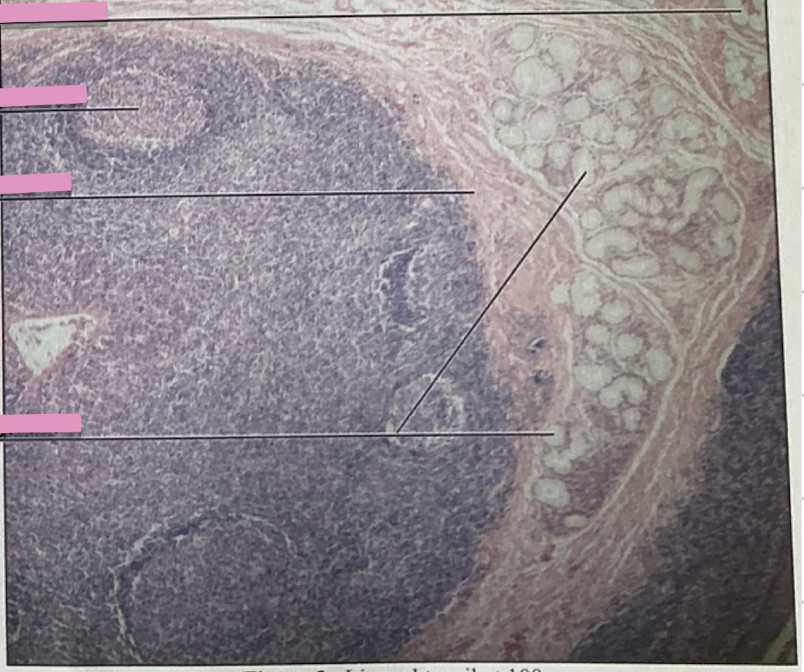

lingual tonsil

palatine tonsil

collections of lymph tissue

back of mouth, tongue, nasopharynx

three tonsil locations

tonsils

_____________ have several lymphoid nodules(covered with stratified squamous epithelium) w/ germinal centers